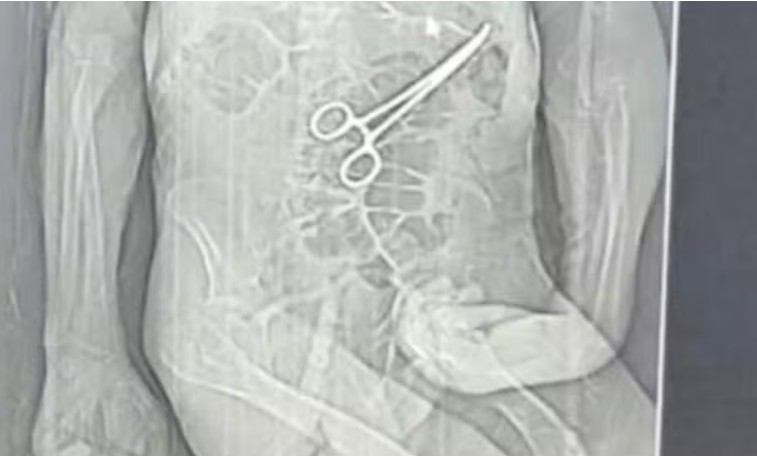

Conforme os familiares, após o segundo procedimento, exames de imagem revelaram a presença de uma pinça tipo “Kelly” no abdômen.